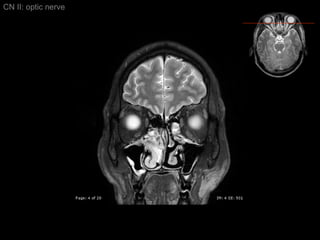

CN II: optic nerve Axial T2/ inferior to superior

CN II: opticnerve Axial T2/ inferior to superior